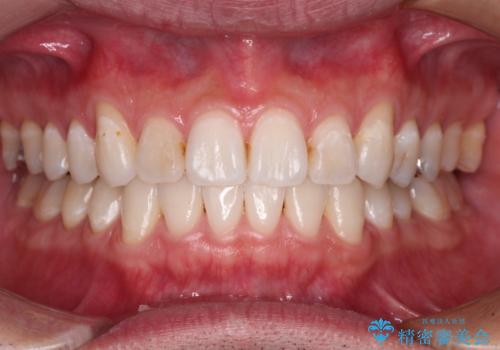

上顎骨拡大を用いたインビザラインによる非抜歯矯正